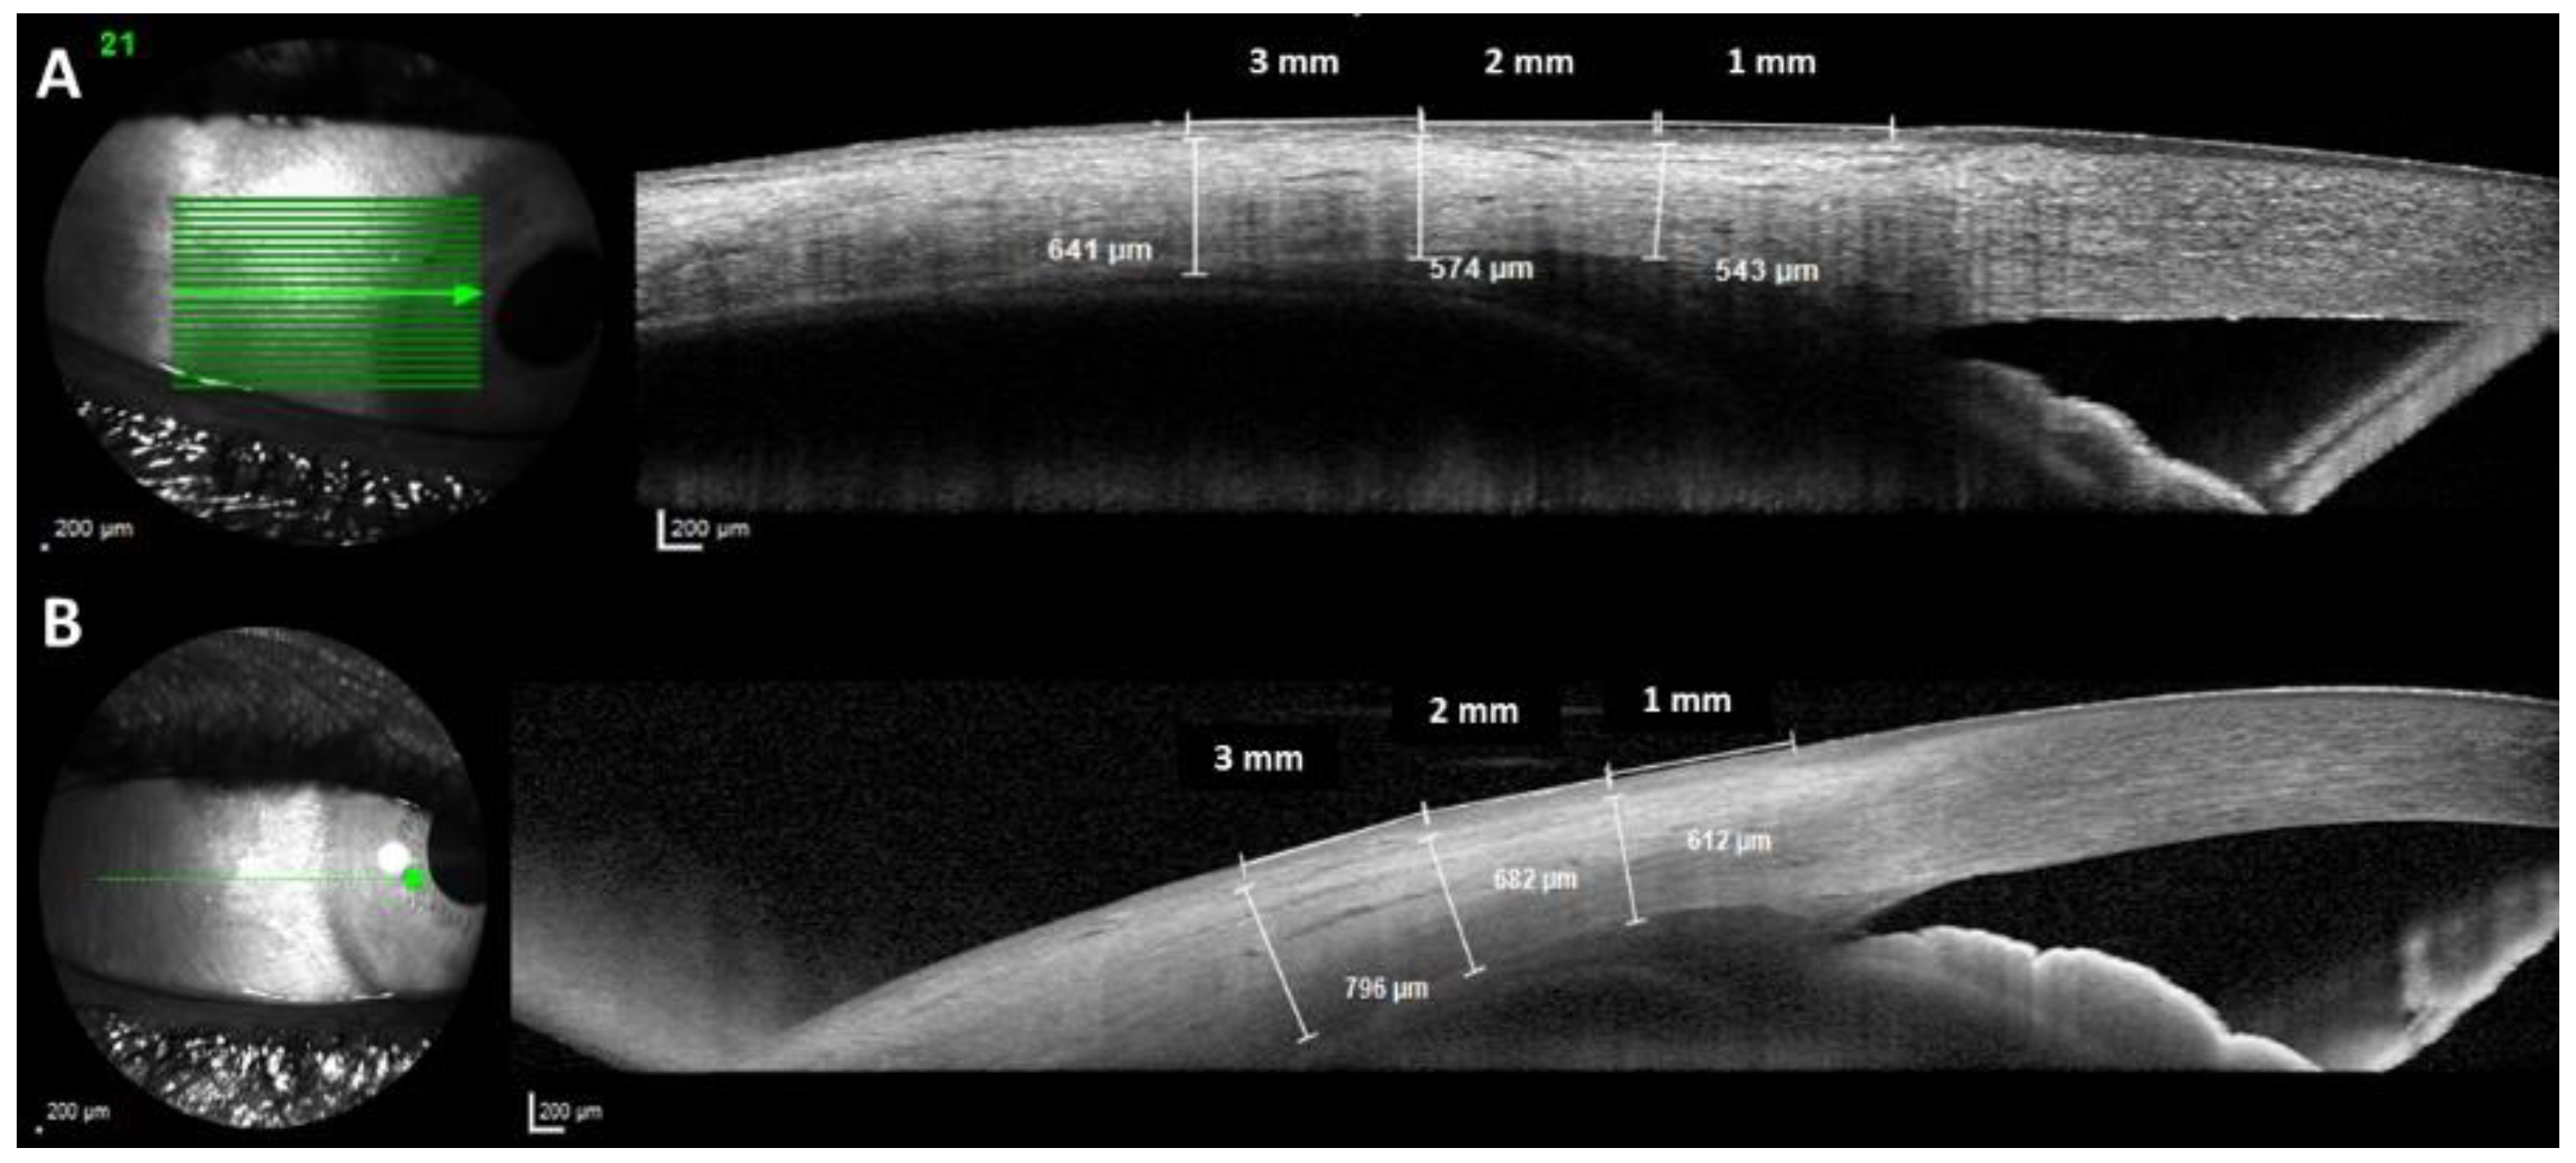

There were no differences in the AST in almost all measurements performed between groups (p ≥ 0.194), except for the nasal AST1 measured by SS-OCT, temporal AST1, and nasal AST3 measured by SD-OCT (p ≤ 0.039) (Figure 3).

Figure 3.

Optical coherence tomography of two examples of nanophthalmic eyes with an especially short axial length (AXL) ((A): 18.5 mm of AXL; (B): 15.94 mm of AXL) showing the anterior scleral thickness (AST) measurements at 1, 2, and 3 mm from the limbus.

Comparing the AST measurements between the eyes with AXL < 20 mm (n = 24) to the ones from ≥20 to <20.5 mm (n = 22), no differences emerged in any of the parameters studied (p ≥ 0.345) (Figure 3).

It is noteworthy that in the present study, the OWT was thicker in all measurement points (at 1, 2, and 3 mm from the scleral spur) and in both quadrants in nanophthalmos eyes (p < 0.001). By contrast, there were no differences in the AST between groups in almost all measurements performed (p ≥ 0.194), except for the nasal AST1 measured by SS-OCT, temporal AST1, and nasal AST3 measured by SD-OCT (p ≤ 0.039). Since the OWT measurements include the AST dimensions, the possible explanation for the difference in OWT measurement could be a thicker anterior choroid or ciliary body in the group of nanophthalmos. Despite being significant from a statistical point of view, we hypothesize that these differences in the range of 10% are probably non-significant from a biological point of view. In addition, Figure 3 shows the AST measurements in nanophthalmic eyes with especially short AXL. In this regard, Kaewsangthong et al. measured the AST in a nanophthalmic patient using a UBM to avoid the influence of uveal leakage and detachment on the RCS measurement results, showing that the scleral thickness at the limbus of this patient was 1.26 mm [20], while the scleral thickness at the limbus of a normal eyeball was 0.53 ± 0.14 mm [21]. Interestingly, Lu et al., using anterior segment SS-OCT in nanophthalmic eyes, found that the morphological features of the aqueous humor pathway, including Schlemm’s canal and trabecular meshwork dimensions, are significantly smaller than those of normal eyes [8]. Therefore, probably the angle closure and aqueous humor pathway changes could be responsible for glaucoma rather than a thick anterior sclera in nanophtalmic eyes.